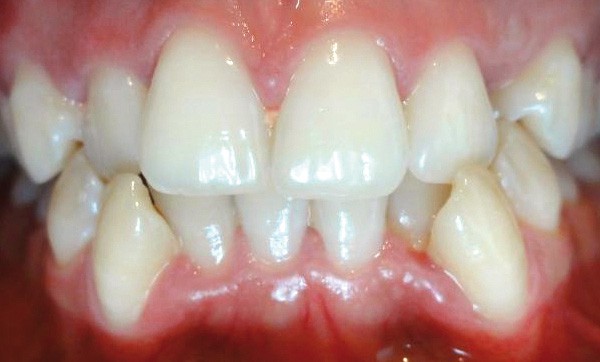

À l’examen endobuccal, on note l’absence de 13 et 23 que la patiente attribue à des avulsions faites en raison de l’ectopie des canines maxillaires. Les espaces de 13 et 23 sont quasiment refermés. La dysharmonie dento-maxillaire (DDM) négative est sévère (fig. 4a et b). La forme d’arcade maxillaire est ovoïde, la forme d’arcade mandibulaire carrée. Les sillons des molaires sont colorés mais non infiltrés.

À l’examen inter-arcades, la patiente présente un décalage des milieux d’origine mixte et est en classe I molaire (fig. 5a à c). Une récession gingivale est à noter sur 33 et 43. Le biotype parodontal est fin avec sans doute une rupture d’attache parodontale liée à la position vestibulaire de 43 et 33. Le contrôle de plaque dentaire pourrait être amélioré sur 16 et 26.